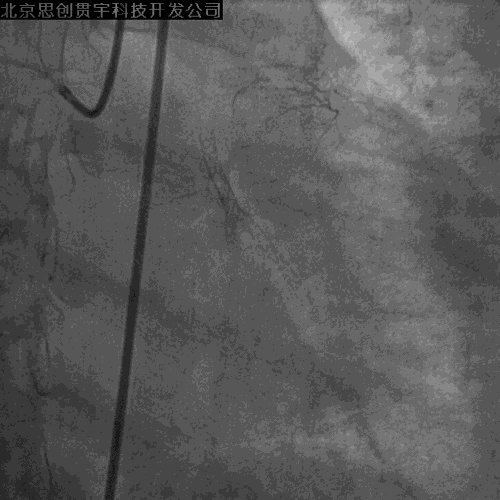

LCX-逆向PCI

PL-左房支-LCX侧枝

Corsair+SION

IVUS引导下UB3+corsair微导管进入正向指引

穿微导管技术送LCX导丝( Modified Rendezvous )